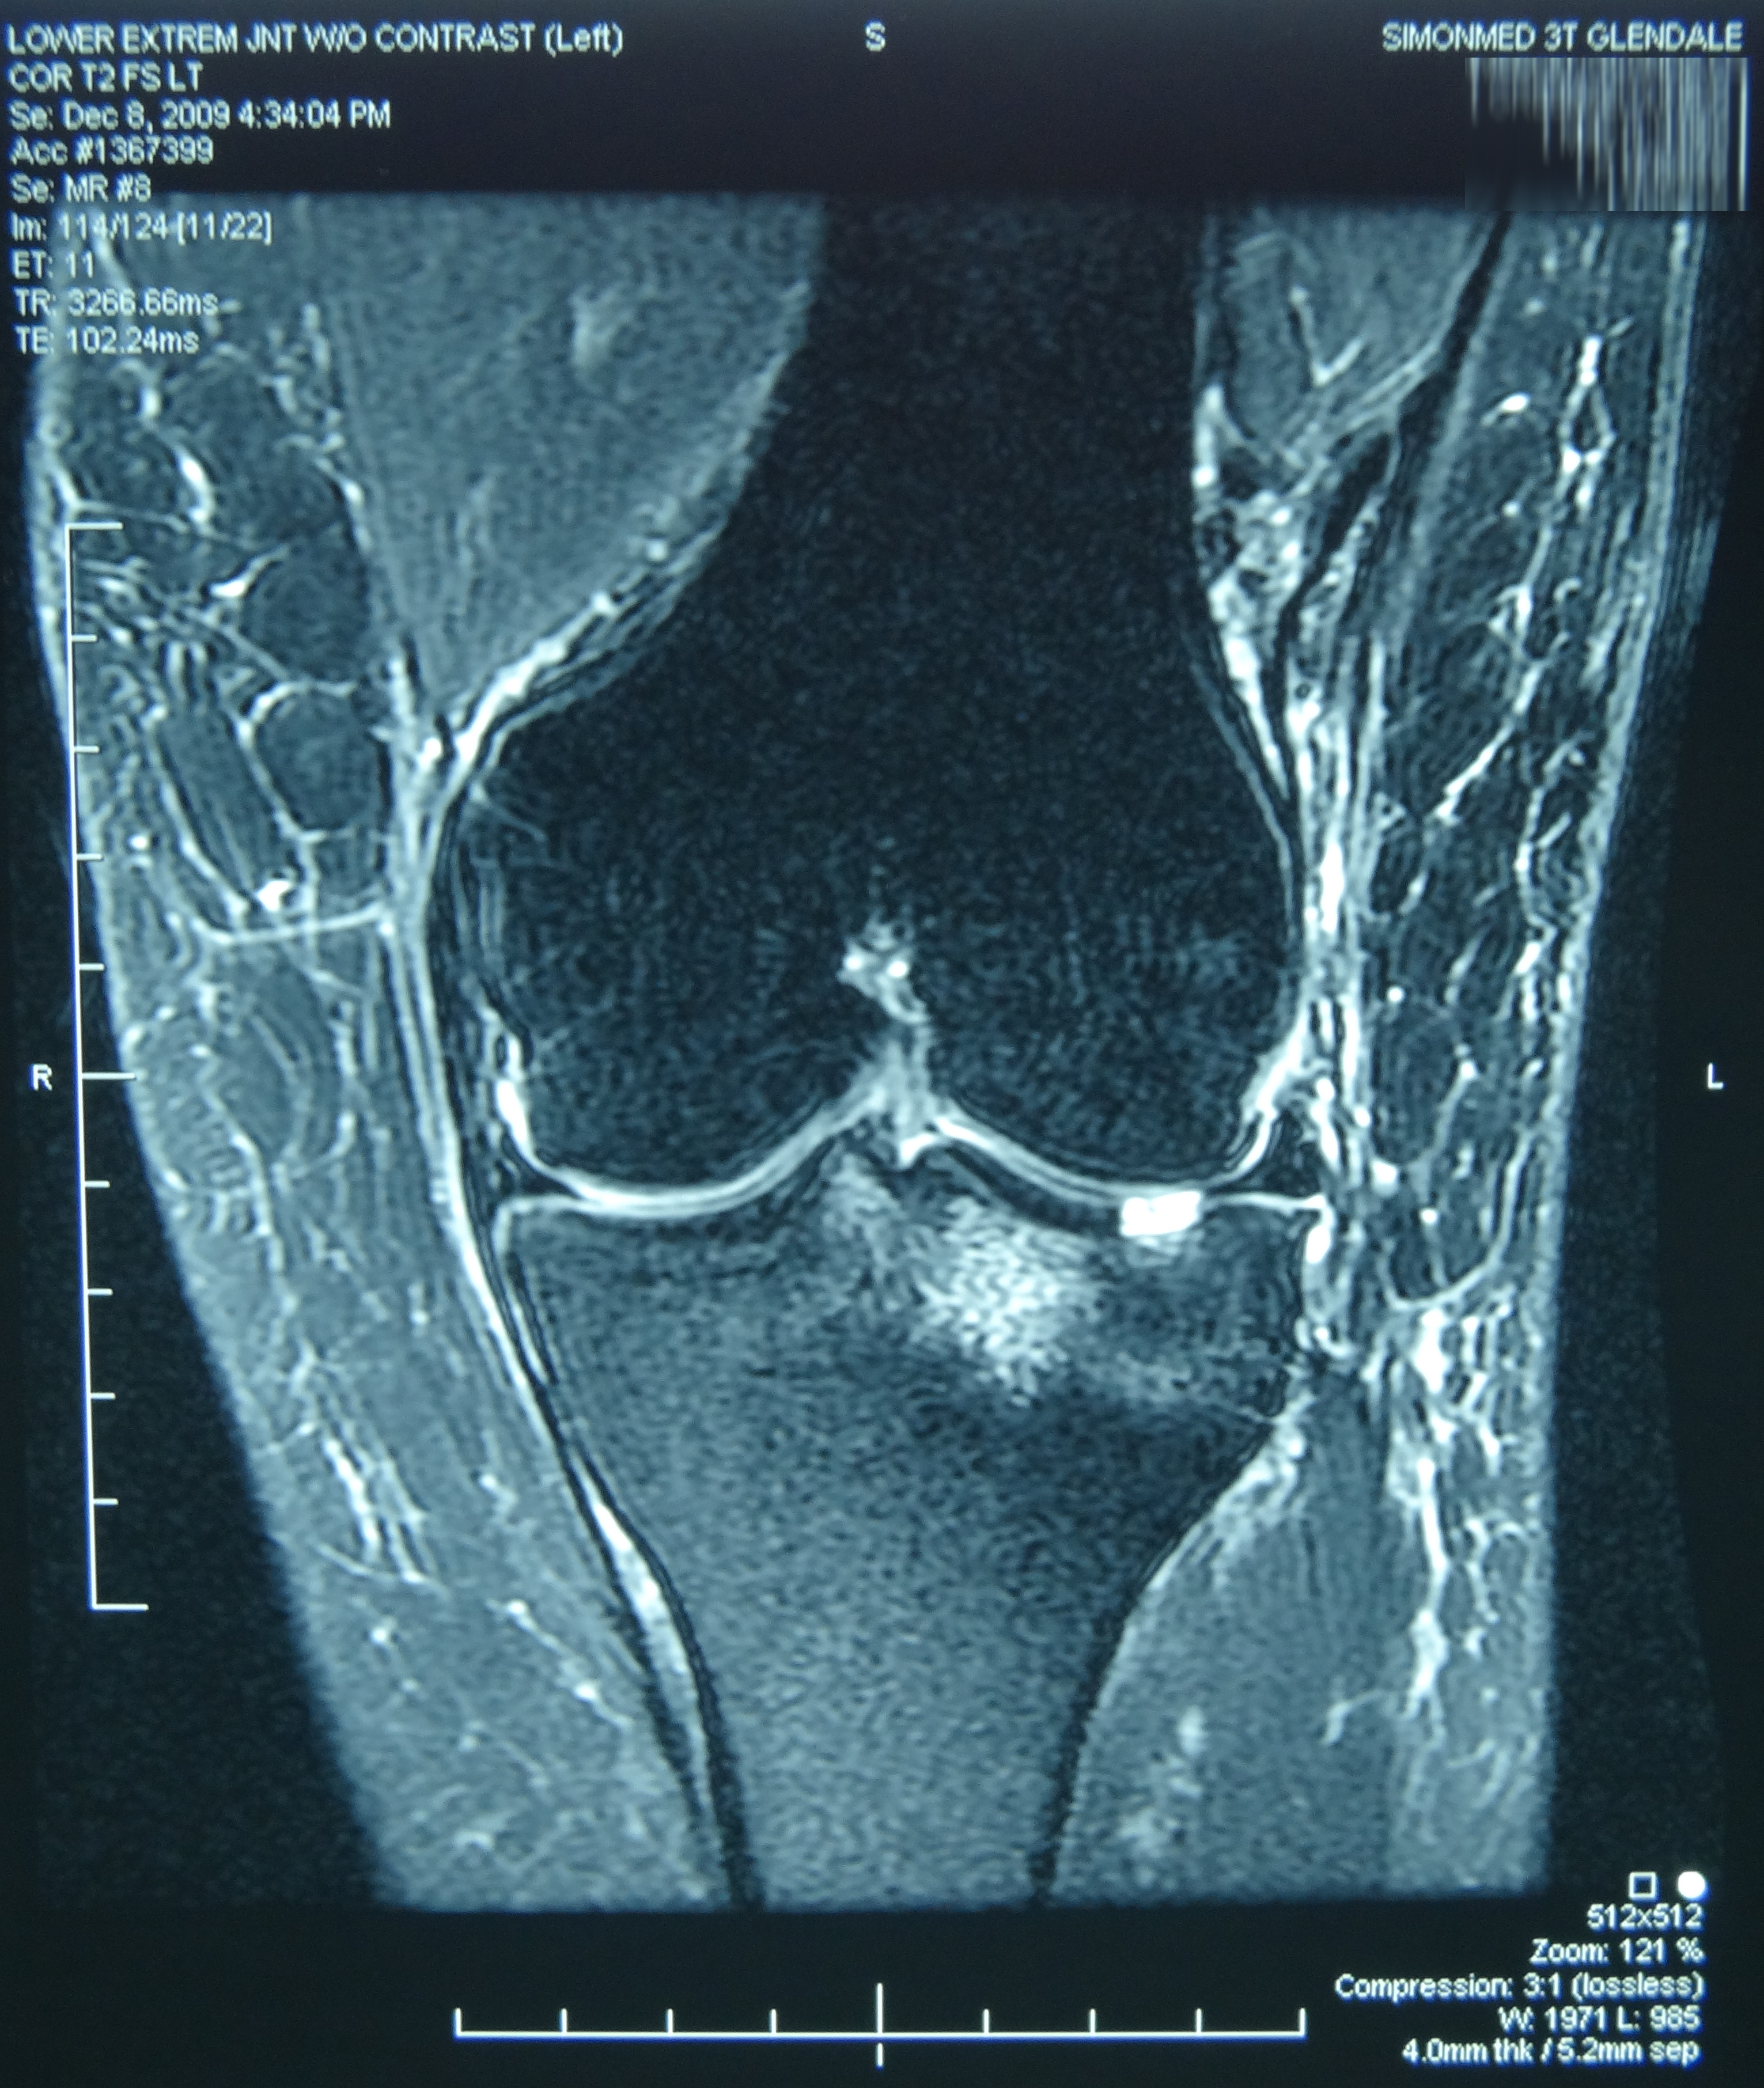

May 2019 MRI

IMPRESSION

- Near full-thickness tear of the anterior cruciate ligament femoral attachment with

associated edema in the intercondylar notch. This is best seen on axial and coronal

images. - Pivot shift bone contusions in a pattern typical of this injury.

- Medial meniscus: Complex tear of the posterior horn of the peripheral third

compromising superior and inferior articular surfaces, with the tear more horizontal

towards the posterior horn/body junction.